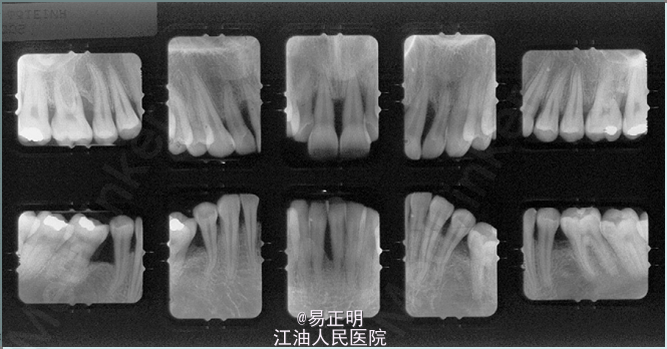

前牙覆HE6mm,覆盖5mm;磨牙Ⅲ类关系;尖牙Ⅱ类关系;上下颌前牙区牙龈退缩;几乎全牙列都有深牙周袋,其中上下颌切牙处最深;探诊出血;患者有磨牙习惯。 上下中切牙和第一磨牙有明显的垂直性骨吸收,牙周医师诊断为侵袭性牙周炎

自锁托槽不需要外物帮助结扎,摩擦力低。不易钩挂食物残渣,托槽体积相对较小,清洁起来相对容易。自锁托槽低摩擦力和持续释放柔和轻力的特点,非常符合牙周病患者的需求。从这个病例治疗后根尖片上可见牙槽骨没有继续吸收,反而有骨质的增生。